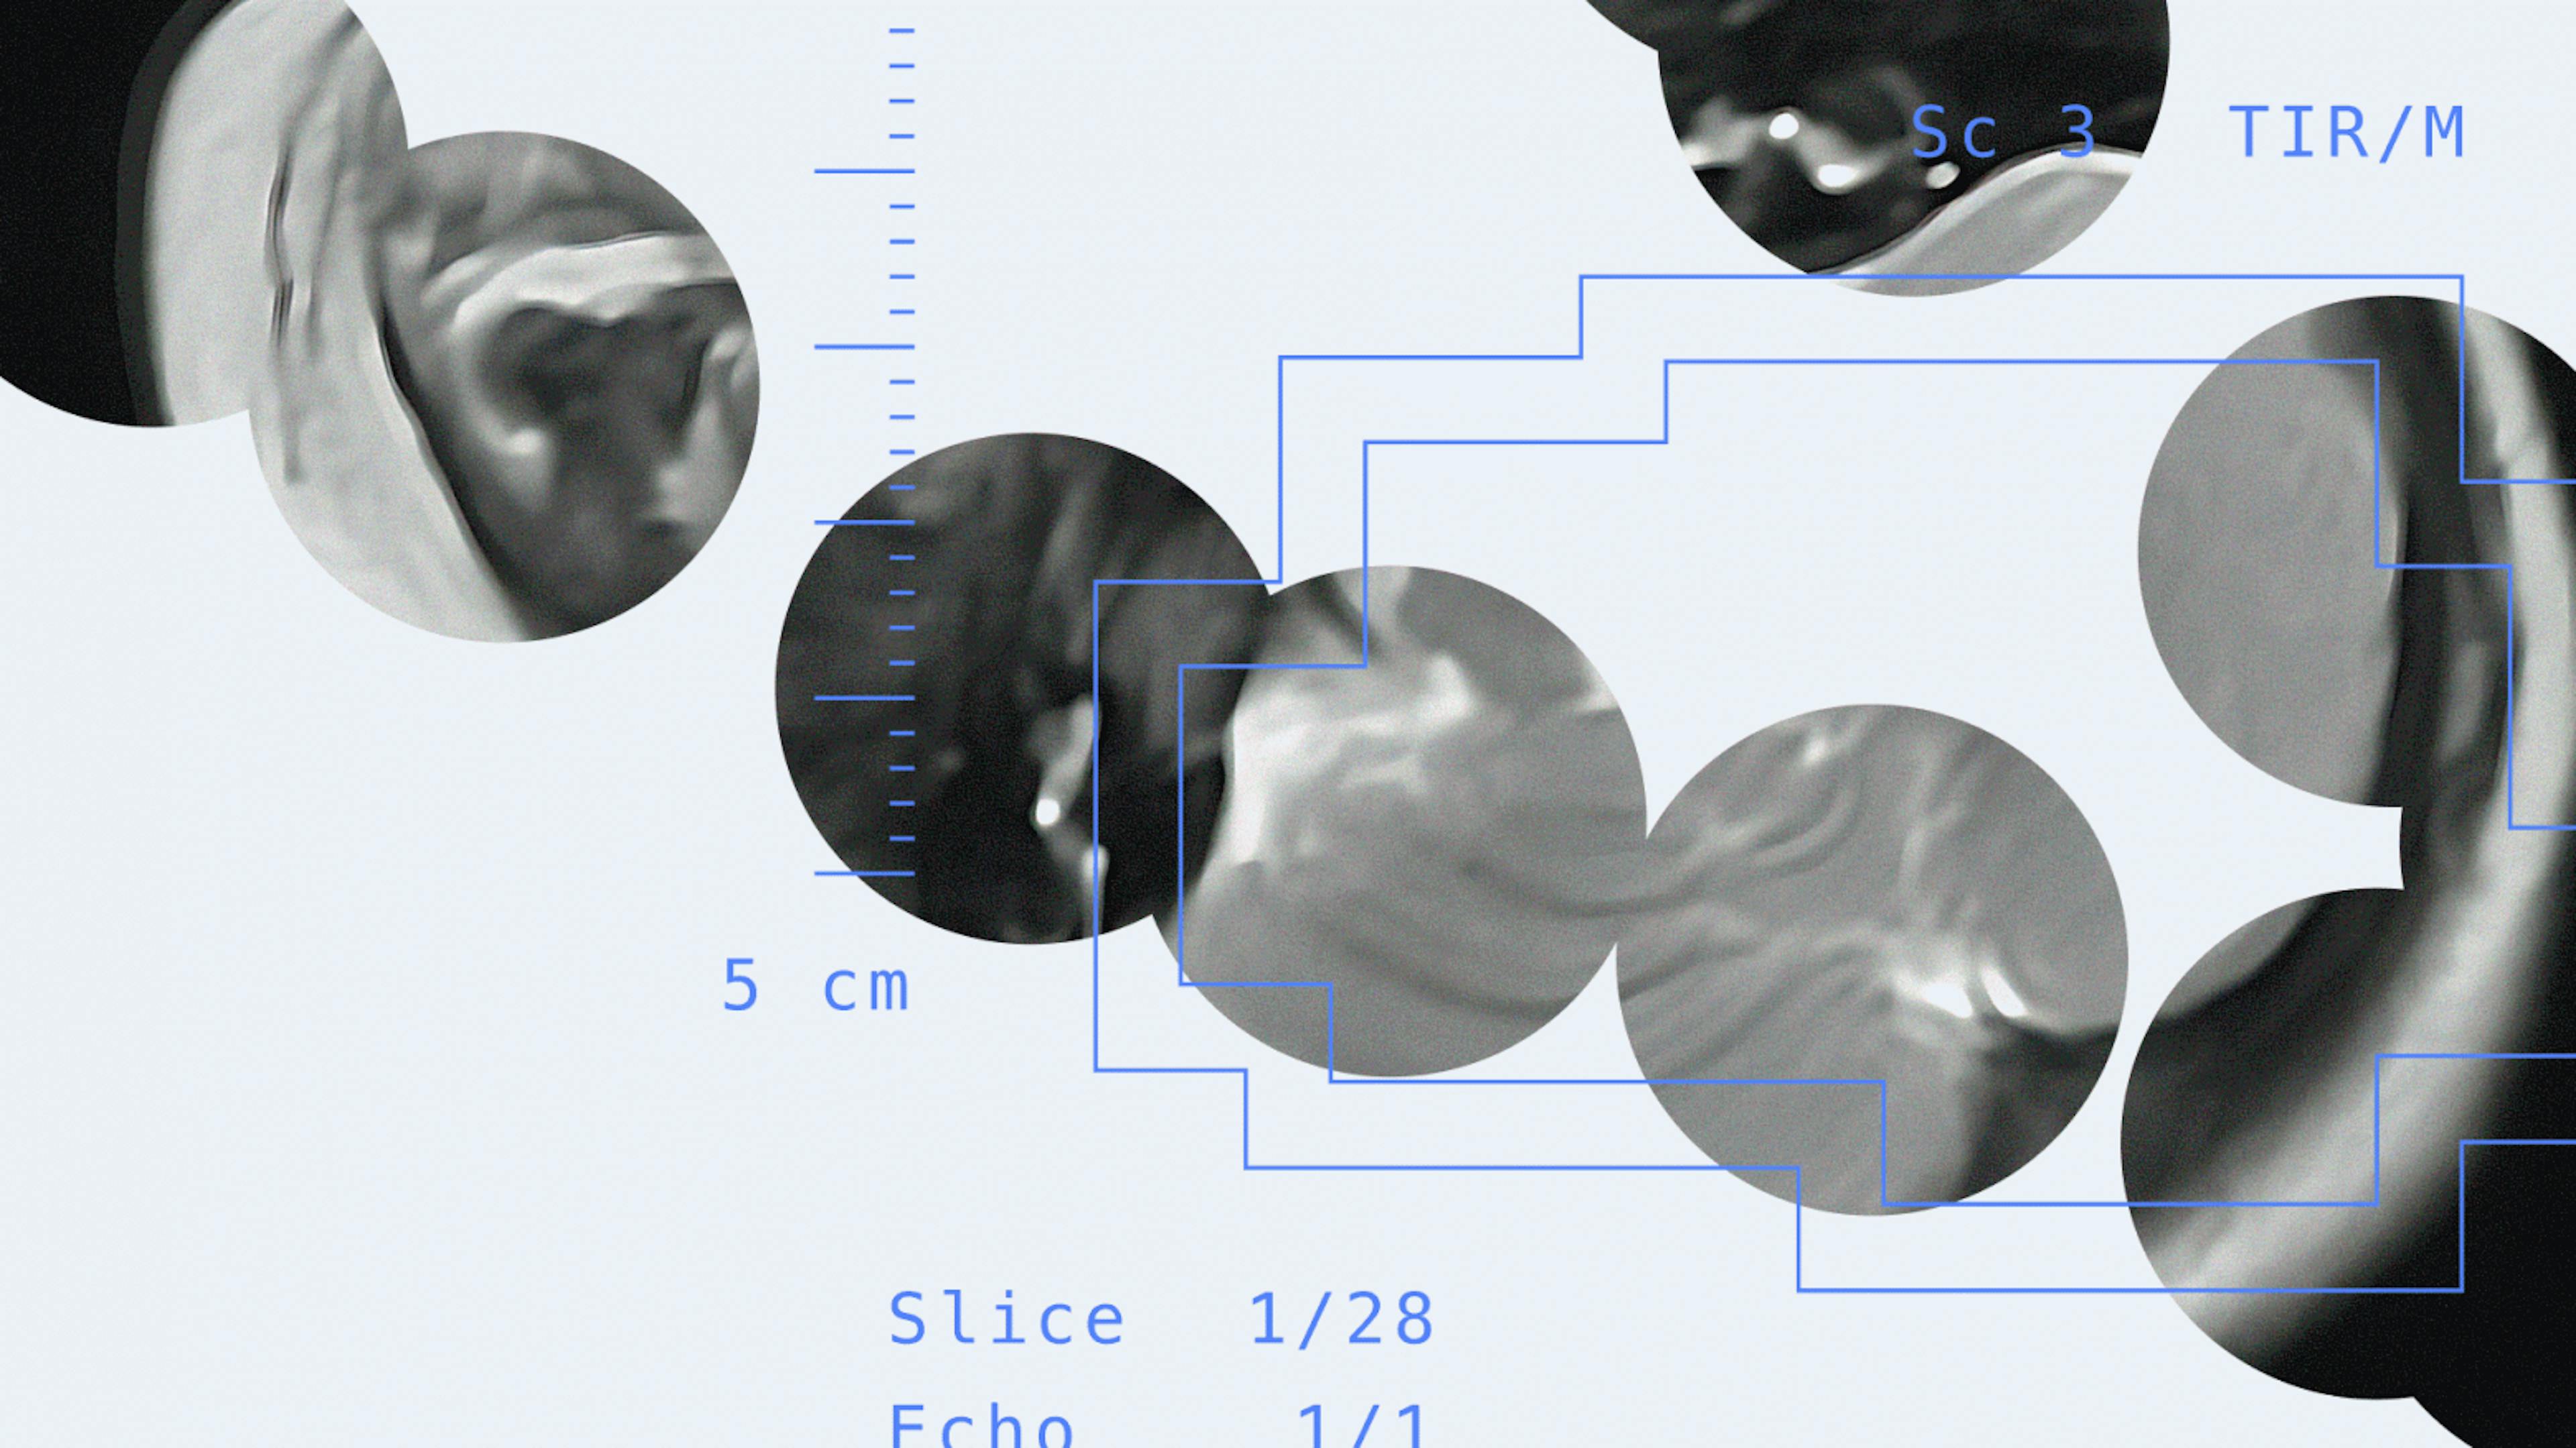

Brain MRIs play a vital role in diagnosing serious health conditions in infants, from tumors to neurodegenerative diseases. Detecting abnormal brain development during infancy can guide early interventions that may prevent or reduce the impact of conditions like cerebral palsy. However, scanning such young patients carries risks, as the procedure requires general anesthesia. That's why doctors need tools that speed up diagnosis, reduce risks, and make timely, informed decisions. Researchers at the Saint Petersburg State Pediatric Medical University partnered with the Yandex School of Data Analysis (SDA) and the Yandex Cloud Center for Technologies and Society to develop an AI solution for assessing infant brain development from MRI scans. For suspected cases of cerebral palsy and other central nervous system disorders, the solution acts as a decision-support tool, reducing MRI analysis time from several days to just minutes. My name is Yulia Busygina, and I'm the project lead at Yandex Cloud. Together with Professor Alexander Pozdnyakov, I'll take you behind the scenes — and share how we designed the AI solution, trained the model, and tested it to see how it performs in real-world scenarios. To learn more about the project, check out ourGithub. Github Why MRI scans are critical for infants An infant's brain develops at an incredible pace, changing almost week by week during the first year of life. But it’s not just about getting bigger — the brain is also going through critical processes collectively known as cerebral development. One of the most important of these is myelination. Myelination is the formation of a lipid-rich sheath around nerve fibers, which increases lipid content and reduces water. This process begins in the fifth month of fetal development and continues at full pace until about age two. In the central nervous system, myelin is found mainly in white matter, where it acts as an electrical insulator. Healthy myelination allows for a rapid, reliable communication between neurons in the later years. If the brain develops more slowly than expected, it can lead to developmental delays. Тhe human brain is a complex system that requires careful attention from the very first days of life. Disorders can arise if brain growth is either too slow or too fast.Moreover, the complexity goes beyond growth rate. In some conditions, the brain's volume remains unchanged while its tissue density shifts. Whether myelination is abnormally slow or excessively fast (hypermyelination), it can create conditions that lead to neurological disorders. — Alexander Pozdnyakov, MD, Professor and Head of the Department of Medical Biophysics, Saint Petersburg State Pediatric Medical University. Myelination is the formation of a lipid-rich sheath around nerve fibers, which increases lipid content and reduces water. This process begins in the fifth month of fetal development and continues at full pace until about age two. In the central nervous system, myelin is found mainly in white matter, where it acts as an electrical insulator. Myelination Healthy myelination allows for a rapid, reliable communication between neurons in the later years. If the brain develops more slowly than expected, it can lead to developmental delays. Тhe human brain is a complex system that requires careful attention from the very first days of life. Disorders can arise if brain growth is either too slow or too fast.Moreover, the complexity goes beyond growth rate. In some conditions, the brain's volume remains unchanged while its tissue density shifts. Whether myelination is abnormally slow or excessively fast (hypermyelination), it can create conditions that lead to neurological disorders. — Alexander Pozdnyakov, MD, Professor and Head of the Department of Medical Biophysics, Saint Petersburg State Pediatric Medical University. Infants with abnormally slow myelination have a higher risk of developing cerebral palsy. Cerebral palsy is one of the leading causes of childhood disability that affects 2–3 out of every 1,000 newborns. Monitoring cerebral maturation in the first six months of life can be crucial for timely intervention. For patients at risk, acting quickly with the right therapies and rehabilitation can prevent damage and halt cell death. Some patients present with conditions that are poorly understood and difficult to classify. But even in these cases, we can anticipate risks and safely intervene in brain development. Such interventions may include medication or brain-stimulation techniques to accelerate maturation when needed, or slow it to normal levels when it's abnormally fast. — Alexander Pozdnyakov, MD, Professor and Head of the Department of Medical Biophysics, Saint Petersburg State Pediatric Medical University. Some patients present with conditions that are poorly understood and difficult to classify. But even in these cases, we can anticipate risks and safely intervene in brain development. Such interventions may include medication or brain-stimulation techniques to accelerate maturation when needed, or slow it to normal levels when it's abnormally fast. — Alexander Pozdnyakov, MD, Professor and Head of the Department of Medical Biophysics, Saint Petersburg State Pediatric Medical University. On MRI scans, myelinated white matter stands out clearly from areas where myelination is incomplete. In patients under 12 months, however, distinguishing white matter from gray matter is often difficult. This is important because gray matter forms the cerebral cortex, the brain's hub for cognitive processes. When radiologists analyze MRI scans during this stage of brain development, they face two main challenges: Differentiating between white matter and gray matter. Determining the volume of gray matter and white matter. Differentiating between white matter and gray matter. Differentiating between white matter and gray matter. Determining the volume of gray matter and white matter. Determining the volume of gray matter and white matter. Through radiologists’ analysis, clinicians can study how nerve cells move through white matter toward the cortex, creating the brain's neural pathways. Observing these changes over time reveals whether the cortex is thinning or thickening and if the white matter is fully developed. For infants, an MRI is ordered by the attending physician only when there are serious clinical indications. These may include birth-related nervous system injury, brain trauma, seizures, or suspected epilepsy. Because patients under six years of age require general anesthesia to stay still during the procedure, MRIs are performed on young children only when truly necessary. Here's how the procedure usually goes: The medical team places the patient under general anesthesia, positions them in the MRI scanner, and captures the images. The procedure typically takes about 30 minutes but can last up to 40–50 minutes. These images are then processed. A specialist can calculate the volumes of white matter and gray matter using a three-axis formula. Clinical guidelines define the timeframe for this analysis, which can take up to 72 hours in complex cases. The medical team places the patient under general anesthesia, positions them in the MRI scanner, and captures the images. The procedure typically takes about 30 minutes but can last up to 40–50 minutes. The medical team places the patient under general anesthesia, positions them in the MRI scanner, and captures the images. The procedure typically takes about 30 minutes but can last up to 40–50 minutes. These images are then processed. A specialist can calculate the volumes of white matter and gray matter using a three-axis formula. Clinical guidelines define the timeframe for this analysis, which can take up to 72 hours in complex cases. These images are then processed. A specialist can calculate the volumes of white matter and gray matter using a three-axis formula. Clinical guidelines define the timeframe for this analysis, which can take up to 72 hours in complex cases. If it's a follow-up scan, the analysis takes even longer because the data must be evaluated against previous results from different time points. How AI can help Existing methods for assessing brain myelination in children under one year old often involve subjective factors. Experienced radiologists can usually determine from the images whether the white matter volume is sufficient. In straightforward cases, 30 minutes to 2 hours of review directly at the MRI console is adequate, and AI is not needed. The task becomes much more challenging when radiologists need to compare several studies over time. Even a single brain MRI involves reviewing multiple images (at least 22 slices). In complex cases, analyzing more than a thousand images may be necessary, making it impossible to review everything quickly. Computer vision can help radiologists by flagging areas where changes in the contours of white matter and gray matter are most likely. This could also serve as an invaluable training aid for junior doctors and residents. This solution provides several benefits for early-age scanning: Speed up the analysis process. Optimize follow-up schedules to ensure scans are performed only as often as needed, avoiding unnecessary anesthesia. Enhance radiologists’ capacity to examine more patients. Speed up the analysis process. Speed up the analysis process. Optimize follow-up schedules to ensure scans are performed only as often as needed, avoiding unnecessary anesthesia. Optimize follow-up schedules to ensure scans are performed only as often as needed, avoiding unnecessary anesthesia. Enhance radiologists’ capacity to examine more patients. Enhance radiologists’ capacity to examine more patients. At first glance, it might seem like we could simply reuse available open-source datasets and pretrained models for this purpose. After all, similar problems have already been tackled using AI in machine learning competitions. For example, the 2019 MICCAI Grand Challenge focused on segmenting MRI images of infant brains under six months. Developers from around the world attempted to solve the challenge using the iSeg-2019 dataset. After all, similar problems have already been tackled using AI in machine learning competitions. For example, the 2019 MICCAI Grand Challenge focused on segmenting MRI images of infant brains under six months. Developers from around the world attempted to solve the challenge using the iSeg-2019 dataset. MICCAI Grand Challenge MICCAI Grand Challenge However, the existing dataset lacked the necessary annotations — the segmentation masks that identify which areas of an image correspond to gray matter or white matter. The iSeg-2019 dataset included only 15 annotated images, while the university's six-year archive contained MRI scans from 1500 patients with no annotations at all. This meant our first step was preparing the data. How to turn MRI scans into a dataset for machine learning The Yandex Cloud team came up with a cloud-based application architecture, helped select the right tools, and assisted with configuring and testing the final web service. Guided by mentor Arseniy Zemerov, students from the Yandex School of Data Analysis handled the core ML tasks: choosing the neural network architecture, running experiments, and training the model on the annotated data. The most complex task — data annotation — was a true team effort, with expert radiologists from the Saint Petersburg State Pediatric Medical University providing critical expertise. Here's a high-level overview of the data pipeline. Let's look at the first stage. Loading the raw data. MRI scans are stored in a picture archiving and communication system (PACS) designed for managing medical images in DICOM format. This system archives and processes anonymized scans, which form the core of the model's training dataset. To deploy this system, we set up a virtual machine in Yandex Compute Cloud. We uploaded anonymized MRI studies of children under 12 months from the university's archive, together with the iSeg-2019 data. Loading the raw data Each study is a collection of MRI images captured in different modes: T1, T2, FLAIR, and DWI. These modes highlight different tissue characteristics, helping clinicians better differentiate between various conditions (for details, see this article). To meet these requirements, this system stores additional metadata and treats multiple MRI slices as a single, unified study. This ensures that no personal data is stored on the server because we work only with an anonymized dataset. this article this article Annotating the collected data. For patients over a year old, radiological brain images can be annotated using automated tools such as the open-source 3D Slicer, which calculates white matter and gray matter volumes. However, these methods are not effective for younger patients. On MRI scans of newborns, even seasoned radiologists may find it hard to distinguish white matter from gray matter, making annotation a meticulous, pixel-by-pixel task. Annotating the collected data Initially, we planned for expert radiologists to annotate the raw data from scratch, but the process proved far too time-consuming: a single study with just a few slices could take eight hours or more. With this manual approach, the experts annotated about 30 studies, each containing three slices. To accelerate the process, our ML specialists proposed performing pre-annotation using an open-source model called Baby Intensity-Based Segmentation Network (BIBSNet). The network is based on the nnU-Net framework and is designed to identify white matter and gray matter. BIBSNet BIBSNet After reviewing the pre-annotation results, we found there was still plenty of room to improve many of the metrics. The inference time for a single volume was about 2.5 minutes. To accelerate the process, the team scaled up the computations: The BIBSNet Docker container was adapted for parallel execution. The container was deployed on 20 virtual machines, each processing data independently. The BIBSNet Docker container was adapted for parallel execution. The BIBSNet Docker container was adapted for parallel execution. The container was deployed on 20 virtual machines, each processing data independently. The container was deployed on 20 virtual machines, each processing data independently. This cut the pre-annotation time for the entire dataset, making it possible to assess the algorithm's performance on it. According to our expert radiologists, pre-annotations were useful in 40% of cases, and that alone helped reduce the manual workload. Our ML specialists also benchmarked BIBSNet’s performance in segmenting gray matter (GM) and white matter (WM) on T1-weighted (sagittal) and T2-weighted (axial) MRI scans. As a result, pre-annotation helped us build an annotated dataset of about 750 slices. This was enough to train and evaluate machine learning models for segmentation and detection. Before running the experiments, we split the dataset into training and validation sets, using the latter to check our metrics. Inside our model training experiments Initially, we planned to try a more advanced architecture, the Vision Transformer. However, we soon realized that this architecture was well-suited for healthcare purposes. The model was prone to hallucinations, which could do more harm than good. So, we chose a segmenter built from two types of neural networks: Convolutional neural networks serve as feature extractors (backbones), adapting well to tasks beyond classification (such as segmentation). Architectures explicitly developed for medical imaging, with the U-Net as the primary choice. Convolutional neural networks serve as feature extractors (backbones), adapting well to tasks beyond classification (such as segmentation). Architectures explicitly developed for medical imaging, with the U-Net as the primary choice. The Yandex School of Data Analysis team aimed to develop a segmentation model that could be as accurate as BIBSNet but deliver a much faster inference time. To achieve this, the students ran a series of experiments on the iSeg-2019 dataset. For the neural network architectures, they examined U-Net, U-Net++, and DeepLabV3. For the feature extraction backbones, they tested ResNet-50, ResNet-101, ResNeXt-50, ResNeXt-101, and DenseNet-161. During the experiments, the team tried several approaches: Training purely on target slices (2D): We trained a 2D segmentation model exclusively on manually annotated slices (the initial 30 studies). However, the small amount of training data limited the model's capacity to generalize. Training on combined iSeg-2019 and target data (3D): The model was trained on a combined dataset that included the fully annotated iSeg-2019 data and our target data. For slices in the target studies without annotations, we applied a mask that zeroed out their contribution to the loss function. This ensured that only annotated slices from the target data were used, preventing errors during training. Training purely on target slices (2D): We trained a 2D segmentation model exclusively on manually annotated slices (the initial 30 studies). However, the small amount of training data limited the model's capacity to generalize. Training purely on target slices (2D): We trained a 2D segmentation model exclusively on manually annotated slices (the initial 30 studies). However, the small amount of training data limited the model's capacity to generalize. Training on combined iSeg-2019 and target data (3D): The model was trained on a combined dataset that included the fully annotated iSeg-2019 data and our target data. For slices in the target studies without annotations, we applied a mask that zeroed out their contribution to the loss function. This ensured that only annotated slices from the target data were used, preventing errors during training. Training on combined iSeg-2019 and target data (3D): The model was trained on a combined dataset that included the fully annotated iSeg-2019 data and our target data. For slices in the target studies without annotations, we applied a mask that zeroed out their contribution to the loss function. This ensured that only annotated slices from the target data were used, preventing errors during training. What we discovered Here's what our experiments with different feature extraction backbones showed: Experiments with the network architecture: The best-performing experiment was training a U-Net with a ResNeXt50 backbone using the DiceLoss function. Here's how the model performs on the validation set. Original study from the validation set: Example output from the algorithm Final metrics: iou void iou GM iou WM iou mean unet_resnext50_32x4d_dice_1 0.981 0.629 0.501 0.703 iou void iou GM iou WM iou mean unet_resnext50_32x4d_dice_1 0.981 0.629 0.501 0.703 iou void iou GM iou WM iou mean iou void iou void iou GM iou GM iou WM iou WM iou mean iou mean unet_resnext50_32x4d_dice_1 0.981 0.629 0.501 0.703 unet_resnext50_32x4d_dice_1 unet_resnext50_32x4d_dice_1 0.981 0.981 0.629 0.629 0.501 0.501 0.703 0.703 The inference speed of the trained neural network running on a CPU is about 3 seconds. How it currently works Our solution, now available on GitHub, was designed as a web service for radiologists performing MRI scans on infants. They can upload the acquired files to the service right after the procedure. The system anonymizes the uploaded data, removing all personally identifiable information, such as the patient's name, from the records. now available on GitHub The solution automatically identifies gray matter and white matter areas on each MRI slice, providing predictions with confidence scores. The service is primarily morphometric, meaning it measures tissue volumes. Once processing is complete, users see the model's predicted volumes of gray matter, white matter, and cerebrospinal fluid, along with descriptions of the largest structures. From the summary table, you can select a specific study to view the scan with the white matter and gray matter masks applied. Our experiments show an accuracy of over 90%. We expect this figure to improve as we expand the dataset and continue fine-tuning the model, which was initially trained on limited data. Looking ahead, the project's roadmap goes beyond basic segmentation. Our next step is to calculate the GM-to-WM ratio, which can provide clinicians with deeper insights. The neural network has been tested at the Saint Petersburg State Pediatric Medical University, and the researchers are ready to share their findings with other medical institutions. The solution reduces MRI interpretation time for radiologists from several days to just a few minutes. Once testing is complete, we plan to release the solution as open source for use in medical institutions and research projects worldwide. The solution also has significant scientific potential. Because infant brain volumes weren't previously measured at scale, no fundamental studies have yet examined changes in brain volume across large cohorts. For various conditions and pathologies, this research can help refine medical care standards.